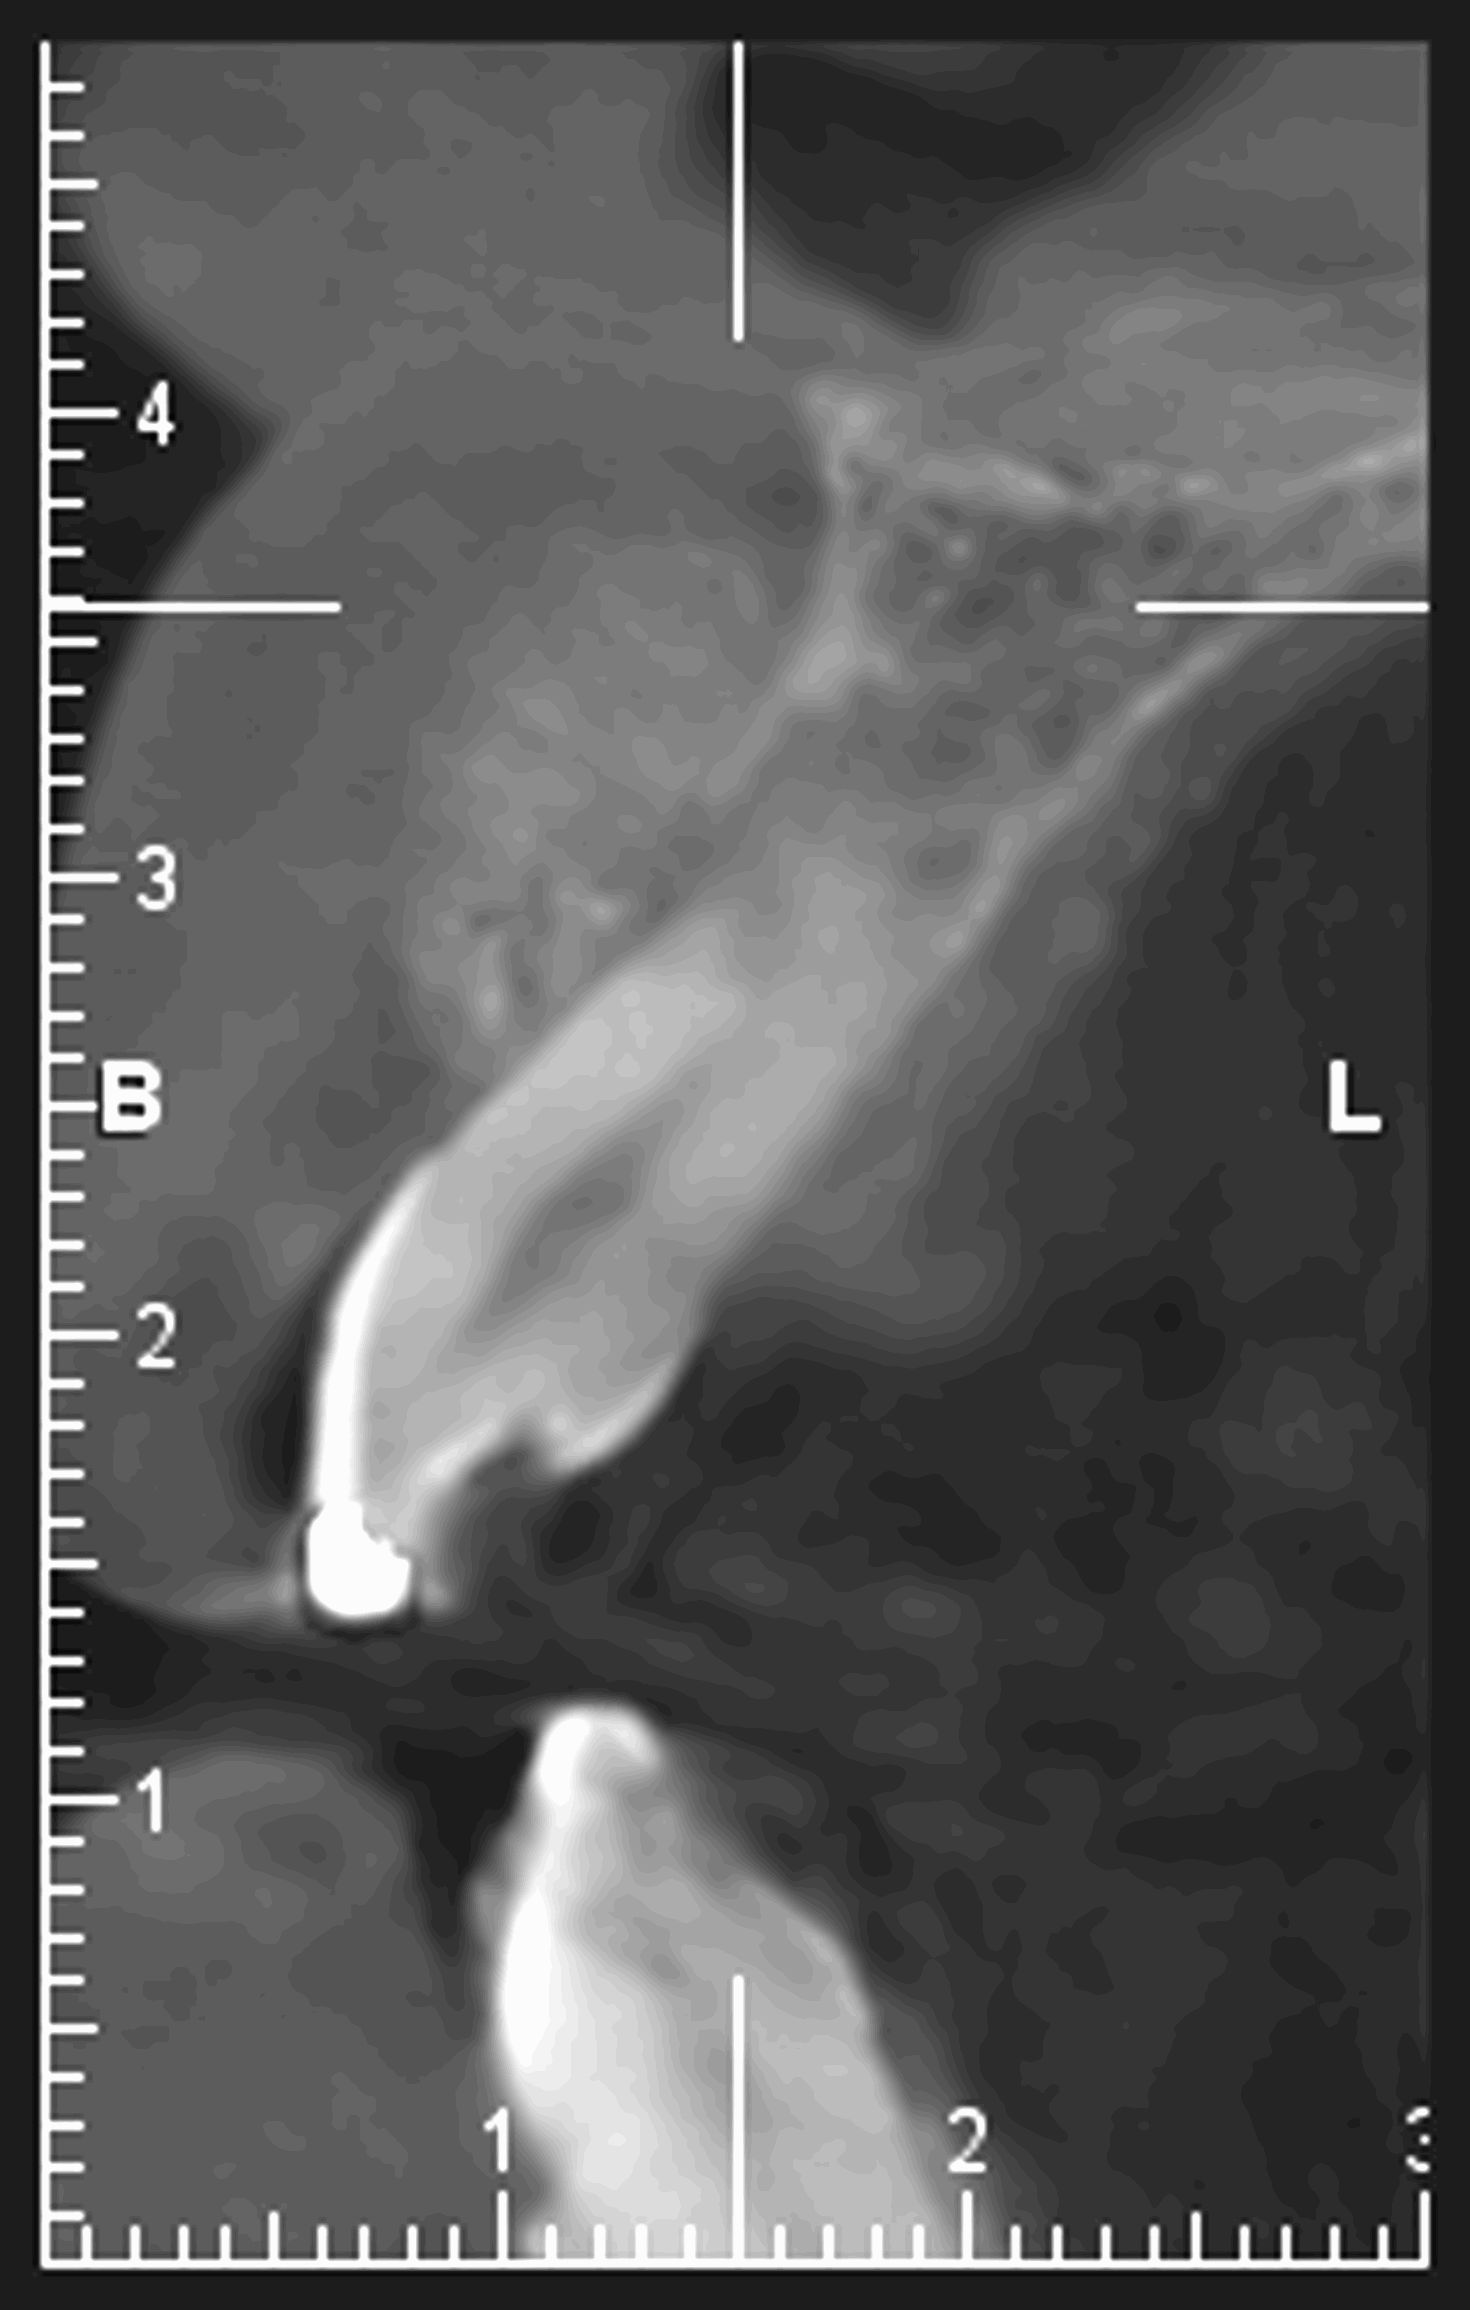

Bilan préchirurgical pour rétrognatisme. La mandibule est en situation trop postérieure par rapport au maxillaire supérieur.

C’est un examen qui permet de visualiser, en rapport 1/1 (1cm sur le film = 1 cm sur le corps), la tête dans son ensemble en superposant sur un seul film les contours osseux, les dents et les parties molles du visage.

Il est possible de réaliser plusieurs incidences:

a) de profil. C’est l’incidence la plus fréquente.